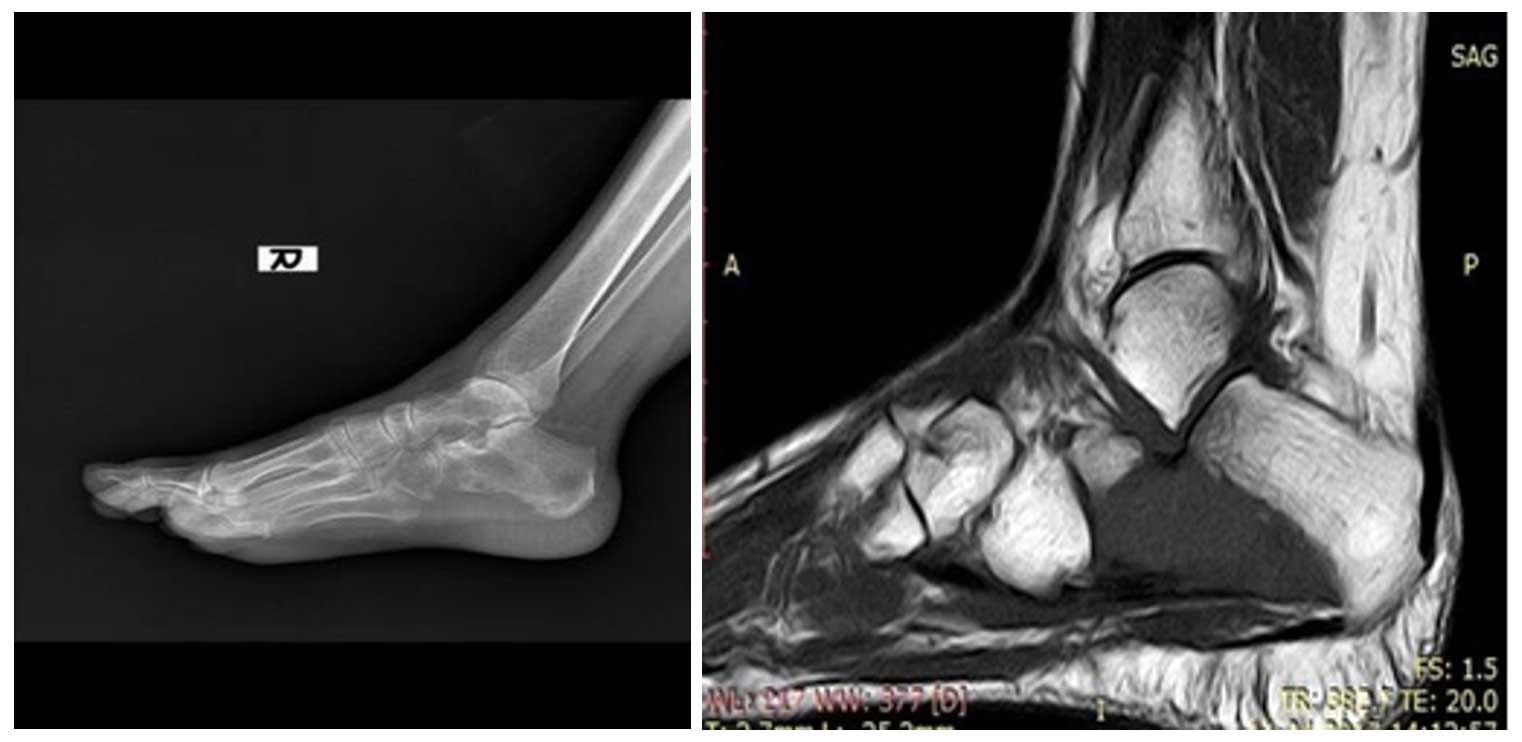

Ameliyat Öncesi: Röntgende sağ topuk kemiğinde yeniklik, MR’da aynı bölgede tümör dokusu görülmekte.

Ameliyat Esnası ve Sonrası: Skopi’de Küret yardımı ile tümörün temizlenmesi ve röntgende oluşan boşluğun kemik çimentosu ile doldurulması görülmekte.